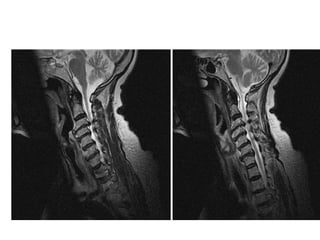

Case based discussions:  68 year old female, Hypertensive and Diabetic. Diabetes is poorly controlled. She presented with 6 months of progressive numbness in the hands and feet. Glove and stocking distribution. There are no other symptoms. Clinically, she has no motor deficits in all 4 limbs but has hyper reflexia. Objective sensory change was mostly in C7/C8 dermatomes bilaterally. Bowel and bladder function and walking were satisfactory.

MRI SCAN SAGITTAL T2W

Surgery performed was an anterior cervical discectomy and fusion using the patients’ iliac bone.  I decided to fuse at two levels C4/C5 and C5/C6 though the main focus was really to do a good decompression of the space behind the C5/C6 disc, which is the site of maximal compression on the MRI scan.